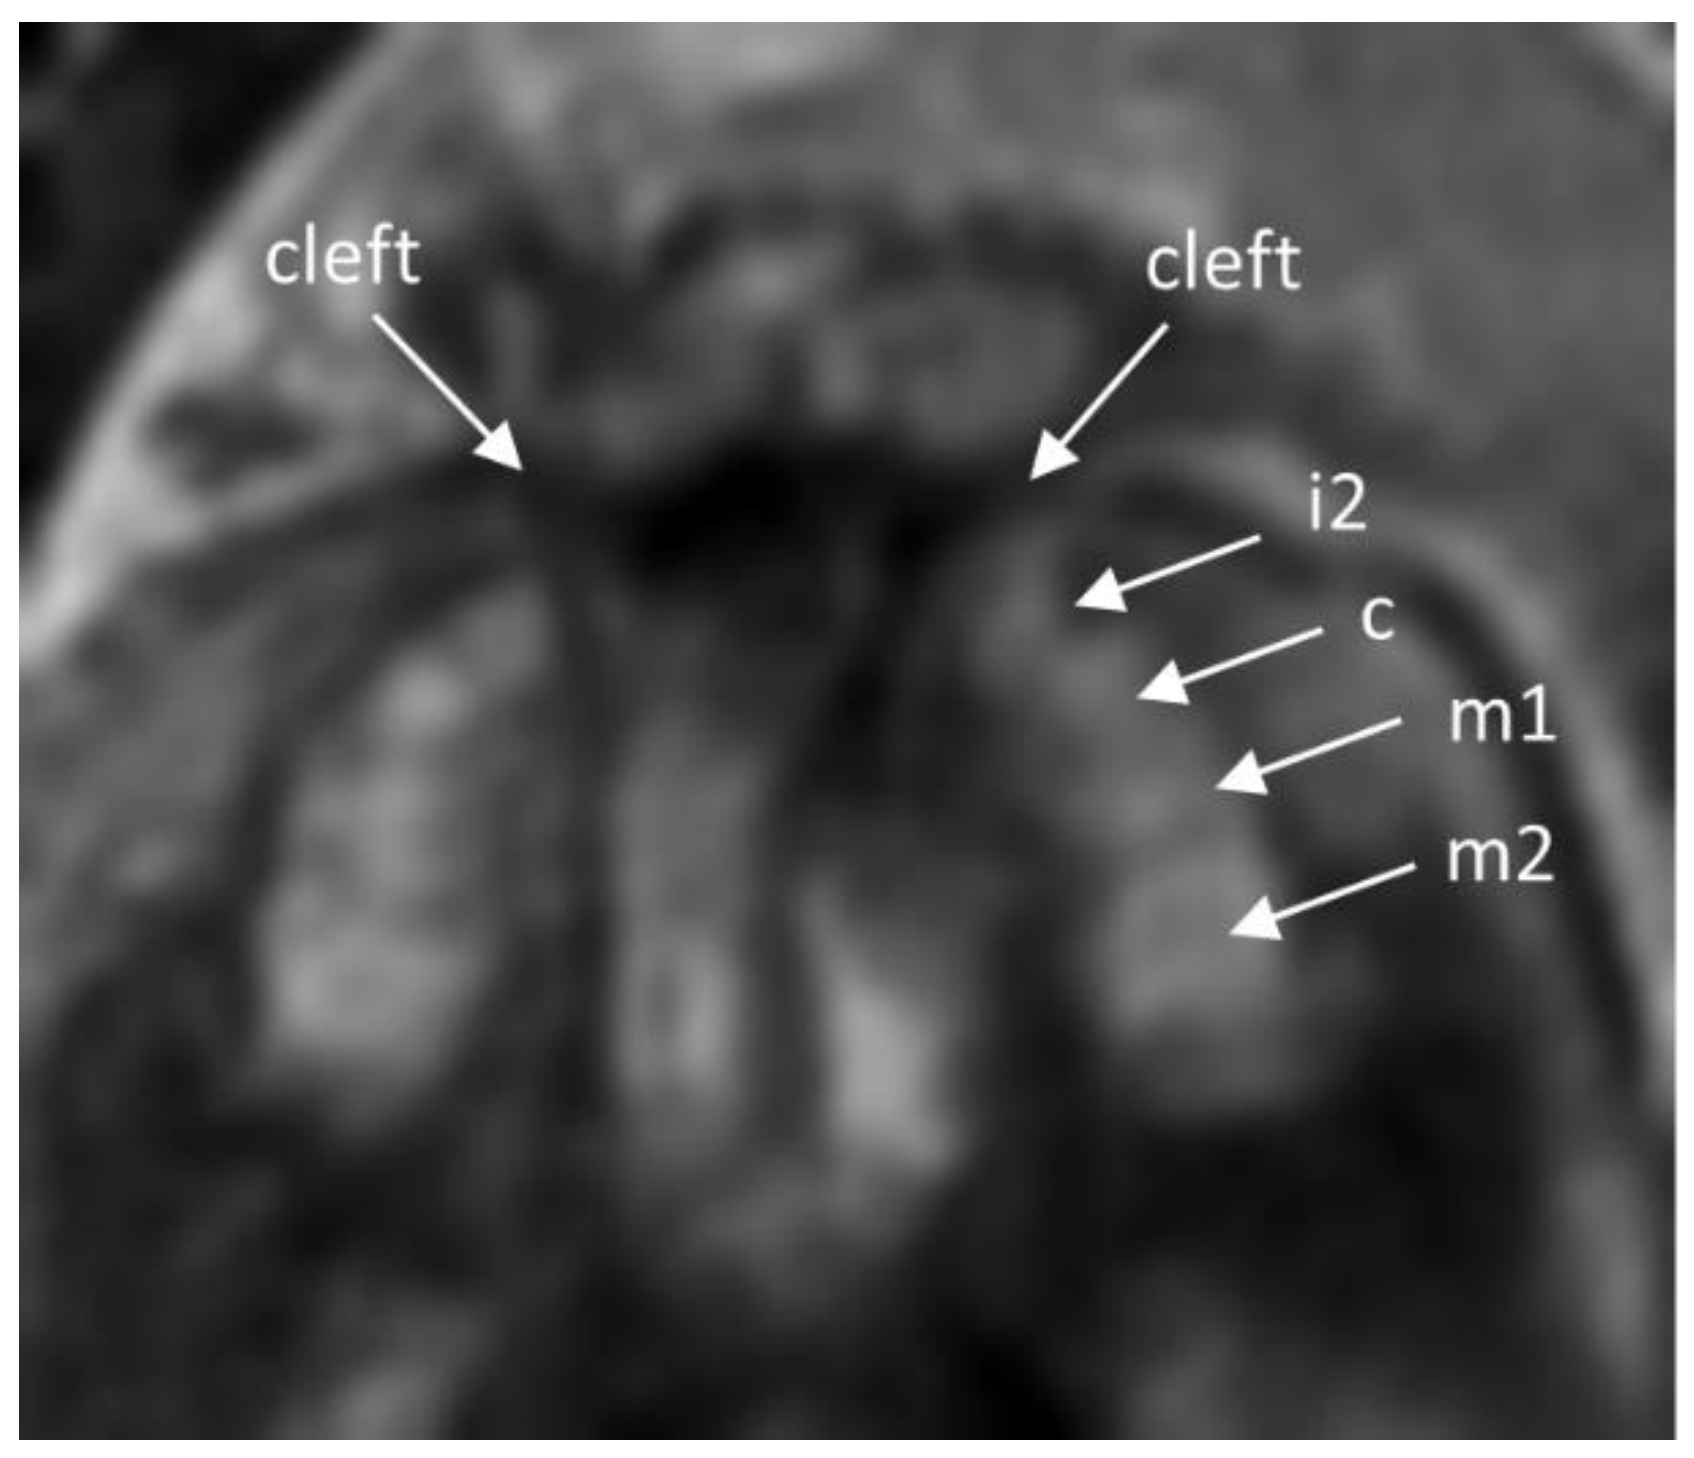

- Mailath-Pokorny, M.; Worda, C.; Krampl-Bettelheim, E.; Watzinger, F.; Brugger, P.C.; Prayer, D. What does magnetic resonance imaging add to the prenatal ultrasound diagnosis of facial clefts? Ultrasound Obstet. Gynecol. 2010, 36, 445–451. [Google Scholar] [CrossRef]

- Mailath-Pokorny, M.; Klein, K.; Worda, C.; Weber, M.; Brugger, P.C.; Czerny, C.; Nemec, U.; Prayer, D. Maxillary dental arch biometry: Assessment with fetal MR imaging. Prenat. Diagn. 2012, 32, 530–535. [Google Scholar] [CrossRef]